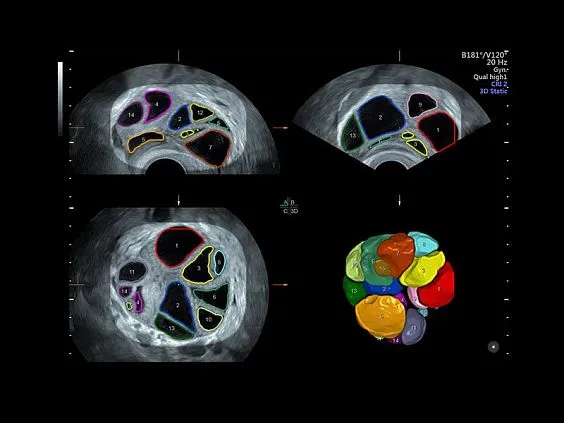

Клинические изображения

- Программа 3D и режим инверсии (при наличии специализированных датчиков).

- Программа объемной визуализации плода классический HD-Live + пакет Hdlive Silhouette — «Силуэт», который включает:

- HDlive Flow — перемещаемый источник света, совместимый с визуализацией кровотока в 3D.

- HDlive Silhouette — режим «Силуэт» с подчеркиванием границ тканей и объектов, «объем в объеме».

- HDlive Flow Silhouette — режим «Силуэт» с выделением границ полостей сердца и сосудов, совместимый с визуализацией кровотока.

- Автоматическое определение плода в режиме 3D (SonoRenderLive) — позволяет значительно экономить время и получать изображение конечностей и лица плода в режимах 3D без артефактов и помех — система автоматически определяет границы конечностей и лица плода и выстраивает объемное изображение.

- Программа 3D и режим инверсии (при наличии специализированных датчиков).

- Программа объемной визуализации плода классический HD-Live + пакет Hdlive Silhouette — «Силуэт», который включает:

- HDlive Flow — перемещаемый источник света, совместимый с визуализацией кровотока в 3D.

- HDlive Silhouette — режим «Силуэт» с подчеркиванием границ тканей и объектов, «объем в объеме».

- HDlive Flow Silhouette — режим «Силуэт» с выделением границ полостей сердца и сосудов, совместимый с визуализацией кровотока.

- Автоматическое определение плода в режиме 3D (SonoRenderLive) — позволяет значительно экономить время и получать изображение конечностей и лица плода в режимах 3D без артефактов и помех — система автоматически определяет границы конечностей и лица плода и выстраивает объемное изображение.

- Режим 4D — трехмерное сканирование в реальном масштабе времени.

- Томографический ультразвук (TUI).

- SonoVCADHeart — программное обеспечение для исследования сердца плода в режиме 3D/4D (быстрый доступ к плоскостям сканирования) по рекомендациям ISUOG.

- SonoAVC (Sonography based Automated Volume Count analysis) — программа для автоматического расчета размеров и объема анэхогенных образований/структур в режиме объемной реконструкции. Включает программу для расчета фолликулов и программу для расчета других анэхогенных структур.

Главное достоинство Voluson E8 — качество изображения. Система обеспечивает превосходную чёткость и контрастность как в двухмерном, так и в трёхмерном и четырёхмерном форматах. Она оснащена современными допплеровскими режимами для анализа кровотока и передовыми инструментами трёхмерной реконструкции. Встроенные интеллектуальные алгоритмы автоматизируют многие процессы, что позволяет врачу работать быстрее и точнее.

УЗИ аппарат Voluson E8 оснащён фирменным пакетом технологий HDlive, который формирует реалистичные изображения благодаря использованию многоточечных источников света и объёмного моделирования.

HDlive Silhouette обеспечивает прозрачность тканей, позволяя рассматривать внутренние структуры.

HDlive Studio формирует максимально приближённое к реальности изображение с несколькими источниками освещения.

HDlive Flow и Flow Silhouette помогают детально визуализировать сосудистую сеть и анатомические особенности кровотока.

Кроме того, аппарат поддерживает Advanced VCI (Volume Contrast Imaging) для оптимизации толщины срезов и повышения контрастности в объёмных исследованиях, а также технологию OmniView, которая позволяет получать изображения в нестандартных плоскостях при анализе сложных объектов.